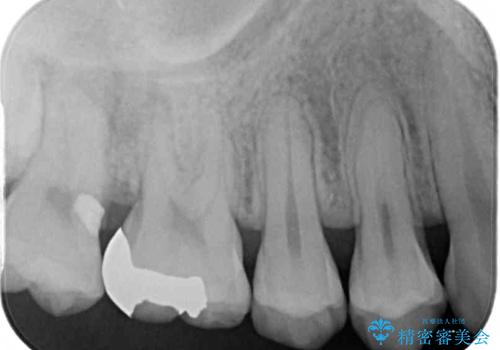

また、奥歯の銀歯をゴールドにしたいとのことで、並行してPGAインレーにて修復治療を行うこととしました。

- インレーおよびクラウンは脱離するリスクがあります

- 形成量はセラミックより少ないですが、歯の形成、修復後に歯に症状が出ることがあります